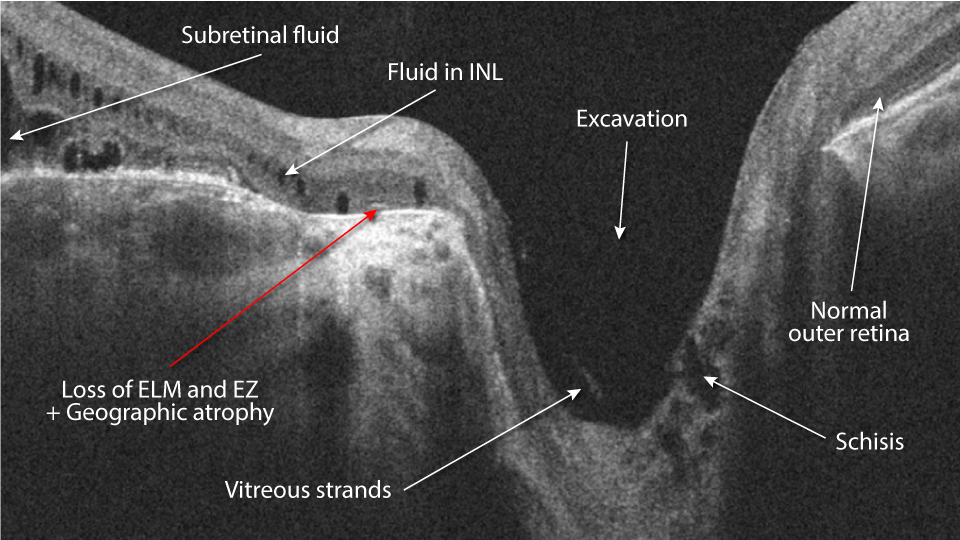

Get the next level OCT learning experience: video analysis with expert commentary, including an extensive case discussion, deep insight, and clinical pearls.

Diagnostic Confidence

Our searchable atlas contains over 100 must-know cases. Grow your knowledge in all areas of eye disease: retina, glaucoma, pediatrics, anterior segment, neuro, pathology, oculoplastics, and ocular emergencies.